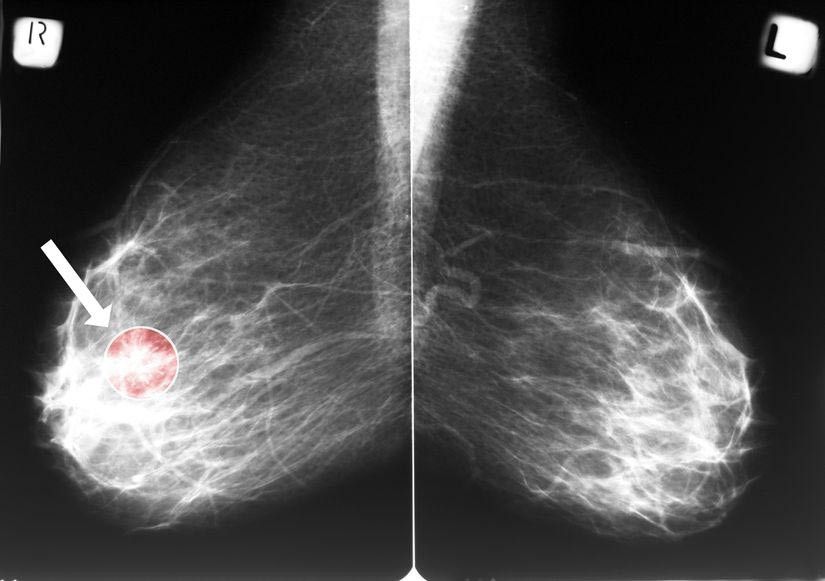

Benjolan fibroadenoma ini dapat diketahui melalui pemeriksaan SADARI jika ukurannya cukup besar untuk diraba, atau melalui pemeriksaan mamografi jika ukurannya terlalu kecil dan tidak teraba pada pemeriksaan fisik.